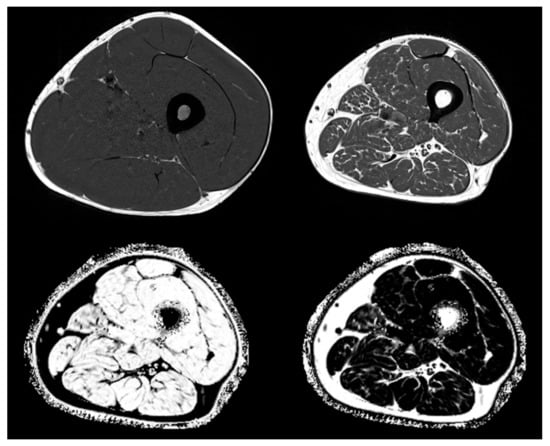

- Grimm, A.; Meyer, H.; Nickel, M.D.; Nittka, M.; Raithel, E.; Chaudry, O.; Friedberger, A.; Uder, M.; Kemmler, W.; Engelke, K.; et al. Repeatability of Dixon magnetic resonance imaging and magnetic resonance spectroscopy for quantitative muscle fat assessments in the thigh. J. Cachex- Sarcopenia Muscle 2018, 9, 1093–1100. [Google Scholar] [CrossRef] [PubMed]

| MRI T1 | thigh abdomen paraspinal muscle | SAT, VAT area/volume (cm2/cm3) IMAT area/volume (cm2/cm3) muscle area/volume (cm2/cm3) |

| MRI Dixon | whole body thigh paraspinal muscle | FF (%) WF (%) |

| CT | thigh abdomen paraspinal muscle | SAT, VAT area/volume (cm2/cm3) IMAT area/volume (cm2/cm3) muscle area/volume (cm2/cm3) muscle density (HU) |